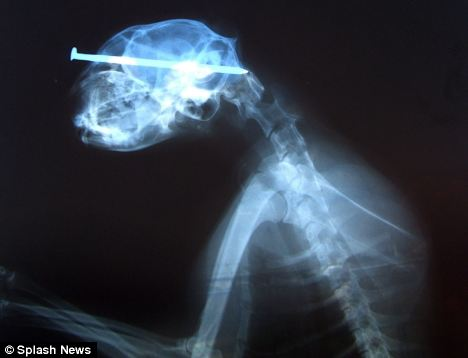

當(dāng)時(shí)照的X光圖

雖然人人都說貓有9條命,但是看到小貓“奇異恩典”頭插8厘米鐵釘在街頭漫步時(shí)你一定還會(huì)驚嘆,貓的生命力真是太強(qiáng)大了!

據(jù)英國媒體5月25日?qǐng)?bào)道,“奇異恩典”生活在美國艾奧瓦州西部港口城市蘇城,盡管頭部被一個(gè)惡棍插進(jìn)去了8厘米長的鐵釘,但它卻什么事兒也沒有,還好端端地在街頭閑逛。

最終,有人發(fā)現(xiàn)了小貓頭部的異物,并將它送到了獸醫(yī)那兒。經(jīng)過手術(shù),獸醫(yī)將它頭上的鐵釘成功拔出。為小貓主刀的辛迪?拉萊特醫(yī)生稱:“我從來沒見過這樣的事,受這么重的傷居然還能和沒事一樣,太神奇了?!?/font>